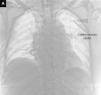

Canalización accidental del cayado aórtico con un catéter venoso central

Accidental cannulation of the aortic arch with a central venous catheter